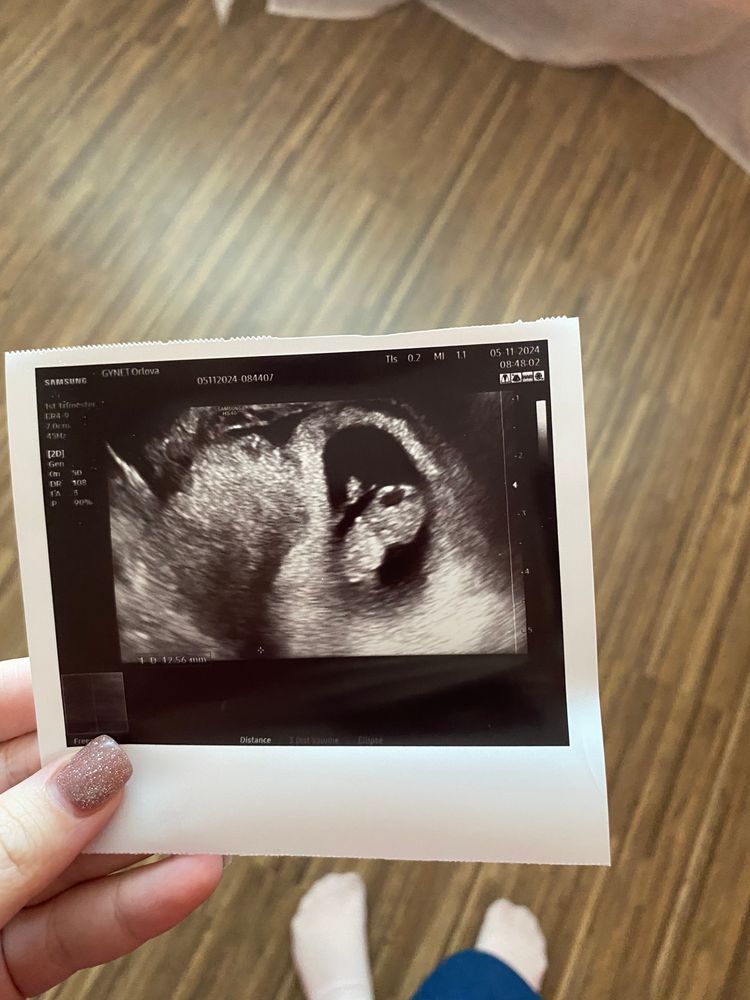

Страхиздравствуйте, девочки может кто сталкивался вчера была на узи , 9 недель беременности, а сегодня только увидела что там черная дырка в голове, вообще не понимаю что это, буду рада ответу 🙏🏻

Это не дырка. Вероятно, полость, где должен быть мозг. Все замеры с точными размерами будут делать на первом скрининга.

Добрый день. Это нормальная картина, формирование мозга происходит из мозговых пузыре, из них формируется передний, средний и задний мозг, а потом формируется полушария и т.д. Ликфорная система выглядит именно так.

Зайдите в группу «Благополучная беременность» и забейте в поиске «УЗИ 9 недель». Там у всех такая «дырка» 🤭 В этом месте будет расположен мозг.

Мне кажется голова наоборот внизу, а это рука опущена вниз, к ноге и образуют кольцо

Возможно это глазные яблоки так выглядят🤔 ну если бы дырка в голове, думаю вам бы сказали точно) кстати не факт, что это голова, возможно и сердце, любое включение выглядит черным